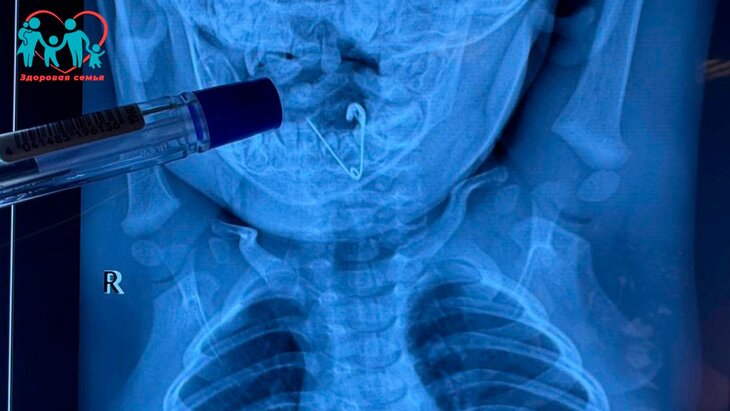

ок проглотил кольцо

Ребенок проглотил кольцо 116 фото